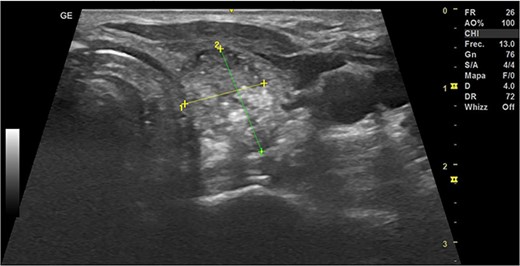

In May 2022, a thyroid ultrasound revealed a solid isoechoic left lobe TN measuring 12 × 11 × 13 mm, characterized by microcalcifications and irregular borders (Fig. 1). The color-flow Doppler ultrasound indicated increased perfusion, leading to its classification as a TI-RADS 5 nodule (Fig. 2). Elastography yielded a value of 2.2 (Fig. 3). Fine-needle aspiration confirmed Bethesda VI, consistent with thyroid papillary carcinoma.

Thyroid ultrasound: transversal view, left lobe nodule identification and measures. Pre-RFA procedure.

During the first-month follow-up, the TN demonstrated a reduction in size to 10 × 14 × 15 mm with a volume of 1.11 cc, indicating a 22% increase in volume compared to the pre-RFA measurements (Fig. 4). Notably, the patient's thyroid function remained preserved.

Thyroid ultrasound: left lobe, transverse view, nodule identification and measures. The first-month follow-up.